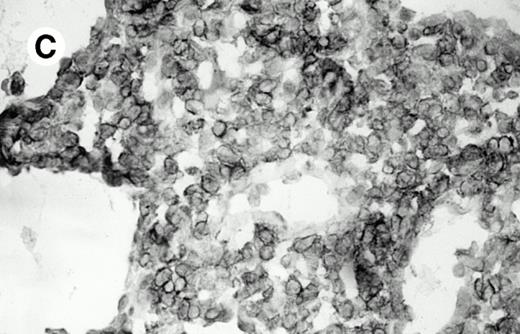

Three cases (cases no. 1 to 3) were located in the nasal cavity. The neoplastic infiltrate consisted of medium and/or large pleomorphic lymphoid cells (Fig 1)intermingled with variable numbers of small lymphoid cells, plasma cells, eosinophils, and histiocytes. Features of angiocentrism and angioinvasion, epitheliotropism, and areas of necrosis were observed in all three cases. Patient no. 4 presented with disease restricted to the lung and an open-lung biopsy was available. The neoplastic infiltrate was composed of large atypical lymphoid cells and was predominantly interstitial without extensive destruction of the normal architecture. Features of angiocentrism, angioinvasion, and epitheliotropism were present (Fig 2A and B). Case no. 5 involved the larynx, extending to the piriform sinus, the ventricle, and the arytenoid. One month later, the lymphoma disseminated to the subcutaneous tissue in the spinal region and biopsy specimens from both sites were available. The neoplastic cells were medium and large, with abundant clear cytoplasm and slightly irregular nuclei with dense chromatin. Epitheliotropism was present in the larynx mucosa. Small foci of necrosis and angiocentrism were seen without angioinvasion. Three patients presented with cutaneous disease. Cases no. 6 and 7 were comparable, as both histories started with necrotic subcutaneous nodules of the thigh, which on histologic analysis were characteristic of cytophagic histiocytic panniculitis without evidence of lymphoma (Fig 3A). Second excisional biopsies of cutaneous nodules obtained 7 and 5 months later, respectively, showed characteristic features of lymphoma in both cases (Fig 3B). However, in case no. 6, skin biopsy specimens showed an epidermotropic PML lymphoma extending to the dermis and the subcutaneous tissue, whereas in case no. 7, the neoplastic infiltrate consisted of a PSC confined to the subcutaneous tissue, admixed with benign histiocytes that showed phagocytosis. Patient no. 8 presented with recurrent skin lesions with spontaneous remission over a period of 10 years. The initial skin biopsies demonstrated an intense epidermotropic neoplastic infiltrate that extended to the superficial and deep dermis composed of atypical PML cells. All cutaneous cases displayed features of angiocentrism, but angioinvasion was observed only in case no. 6 and foci of necrosis in cases no. 6 and 8.

Pulmonary pleomorphic large-cell γδ T-cell lymphoma (case no. 4). (A) Atypical lymphoid cells involve the bronchiolar wall and epithelium; (B) features of angioinvasion; note the preservation of alveolar structures (lung biopsy specimen with hematoxylin-eosin stain); (C) neoplastic cells strongly express TCR γδ. (Immunohistochemical staining on frozen sections with anti-δTCR1 antibody, APAAP technique.)